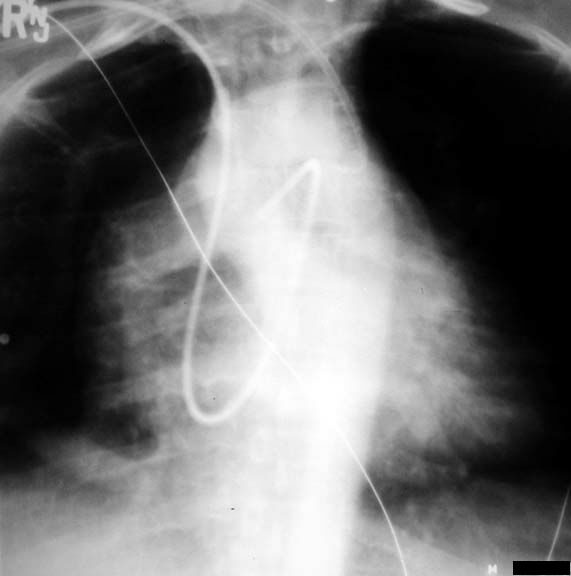

Scimitar Sign

Anamolous pulmonary venous drainage